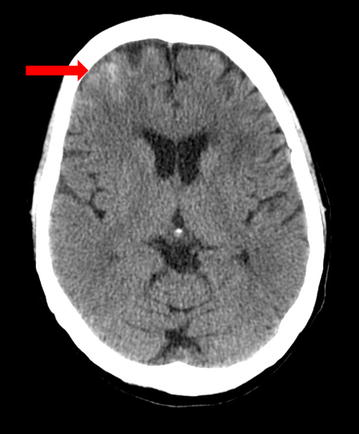

CT of the brain completed right after CEA can be completely normal in patients with CHS. Later on, findings develop which may include diffuse cerebral edema, patchy white matter changes, mass effect, and intracerebral hemorrhage (Fig. 1). These changes are sometimes more marked in the posterior circulation involving posterior parietal-occipital regions as there is a lack of sympathetic innervation in the posterior circulation of the brain. Overall, however, CT brain before or after CEA is of limited value for the evaluation of CHS as such findings can be non-specific. Thus, CT brain is not a useful tool for prediction of CHS [2, 3].

Fig. 1.

CT scan of the brain (axial sequence) shows an area of hyperdensity in the right frontal lobe suggestive of intracerebral hemorrhage (arrow) in a 67 year old woman who underwent right carotid endarterectomy (CEA) for the treatment of a 95 % right ICA stenosis. The patient post-operatively developed headache, photophobia and intermittent dizziness. This CT brain was done almost 24 h after the CEA. Systolic blood pressure was in the 170 s mm Hg and difficult to control as after CEA there was thought to be a clamp injury to the right carotid artery bulb. However, the patient did well clinically and at her 3 month follow up office visit, she had no residual neurological deficits